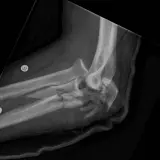

Over 2,100 interactive radiology cases, curated by radiologists for your level of training. Scroll, window, and view cases full screen — just like on PACS. Click linked findings in each writeup to jump straight to them on the image. Cases include sample reports, a focused discussion section, original illustrations, and videos.

Casos totalmente interactivos con las herramientas que esperaría de un PACS: scroll, ventana, zoom, pan, mediciones, ROI y modo de pantalla completa.

• Anotaciones enlazadas

Anotaciones extensas resaltan los hallazgos clave directamente sobre los casos. Haga clic en los hallazgos enlazados dentro de la descripción del caso para saltar a su ubicación exacta en el estudio.

Aprenda con eficiencia gracias a hallazgos de imagen anotados e ilustraciones